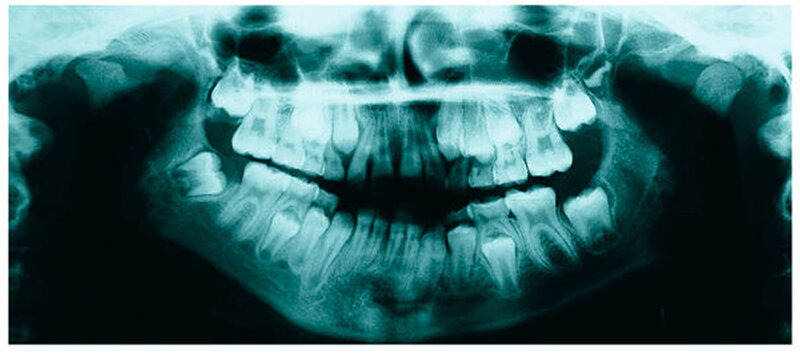

Bereits 2004 wies Carla Evans [Evans, 2005] auf das Risikomanagement bei Allgemeinerkrankungen hin und stellte am Beispiel der JIA dar, dass Unterkieferrücklagen und frontal offene Bisse aus der Kiefergelenkzerstörung entstehen können. Die Röntgenaufnahmen einer JIA-Patientin mit oligoartikulärer Form und Beteiligung des rechten Kiefergelenkes zeigen den typischen Verlauf sehr gut. Bei ursprünglich sehr dezenten Befunden, wie einer s-förmigen Mundöffnung von 44 mm, einer geringen Mittenabweichung um 2 mm nach rechts und einem frontal offenem Biss klagte sie über Schmerzen beim Essen, was den Anlass zur weiteren Diagnostik bot. Die erste Panoramaröntgenschichtaufnahme (Abbildung 1a-c) zeigt auf der rechten Seite einen abgeflachten Kondylus und eine bereits verstrichene Fossa condylaris. Ein Jahr später vermittelt das Fernröntgenseitenbild (Abbildung 1d) trotz fortschreitender kondylärer Resorption ein harmonisches Bild, während nach drei Jahren bei voranschreitendem Abbau des rechten Kondylus (Abbildung 1e) eine Rücklage der Mandibula und eine Bissöffnung manifest sind (Abbildung 1f).

Mithilfe der Panoramaröntgenschichtaufnahme lässt sich in bis zu 67 Prozent der Fälle bereits eine Kiefergelenkdestruktion bei Kindern mit JIA feststellen [Küseler et al., 1998; Twilt et al., 2004; Abramowicz et al., 2014]. Eigene Untersuchungen bestätigten die Eignung als Screening-Verfahren [Mäckelmann, 2008].

Bei 152 durchschnittlich 12-jährigen Rheumapatienten wurden die kondyläre Morphologie und Symmetrie beziehungsweise Asymmetrie im Vergleich zu einer Kontrollgruppe anhand der OPG analysiert. Zur Analyse erfolgte die Zuordnung zu vier morphologischen Graden je Kondylus (Abbildung 3a-d). Bei 45 Prozent der Rheumapatienten waren morphologische Veränderungen im Rahmen kondylärer Resorption unterschiedlicher Ausprägung zu finden. Die „Kontrollpatienten“ ohne JIA zeigten nur zu 14 Prozent formatypische Kondylen. Der Unterschied zwischen den beiden Gruppen war signifikant. Daher sollte bei der Routineauswertung von Panoramaröntgenschichtaufnahmen auf diese Anzeichen geachtet werden, insbesondere auch unter dem Aspekt, dass laut Assaf [2011] durchschnittlich 4,3 Jahre zwischen Erstmanifestation der JIA und Erstvorstellung in der Rheumasprechstunde des UKE liegen.